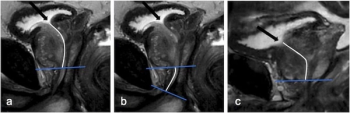

Emerging research findings suggest that a longer prostatic urethral length on MRI is associated with a 70 percent increased risk of grade >2 acute urinary toxicity after radiotherapy for prostate cancer.